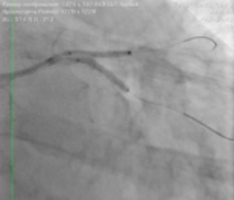

— Мы приняли решение о проведении эндоваскулярной коррекции этого поражения. С помощью двух баллоных катетеров диаметром 2,5 мм была выполнена предварительная дилатация стеноза ствола левой коронарной артерии, устьев огибающей артерии и передней нисходящей артерии по методике «целующихся баллонов». Это одновременное раздувание двух баллонов на бифуркации — успешно применяемое нами прогрессивное техническое новшество. Затем выполнено стентирование по методу culotte с выходом в переднюю нисходящую и огибающую артерии. На контрольной ангиограмме был выявлен критический стеноз в проксимальной трети передней нисходящей артерии, который ранее был маскирован основным поражением. Был стентирован участок в проксимальной трети. На контрольной ангиограмме кровоток в левой коронарной артерии по шкале TIMI — III, что означает оптимальный результат стентирования. Зон диссекций и резидуальных стенозов нет.

![]() Формирование бифуркации по методике «целующихся баллонов» |